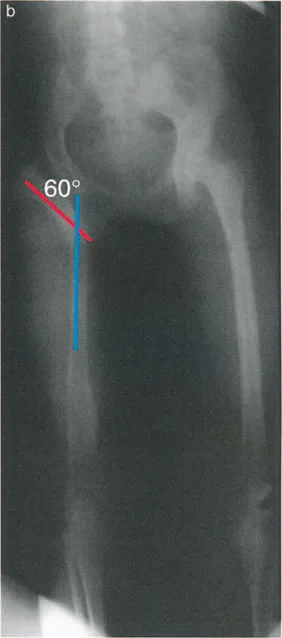

صورة أشعة سينية بعد التخطيط توضح تنفيذ القطع العظمي القريب. تم تطبيق تصحيح تقوس خارجي بزاوية 60 درجة لتوفير دعم قوي للحوض والقضاء على هبوط الحوض.

* تحديد زاوية التقوس الخارجي (Valgus): تُحسب باستخدام معادلة دقيقة: زاوية هبوط الحوض أثناء الوقوف على ساق واحدة + 15 درجة تصحيح زائد.